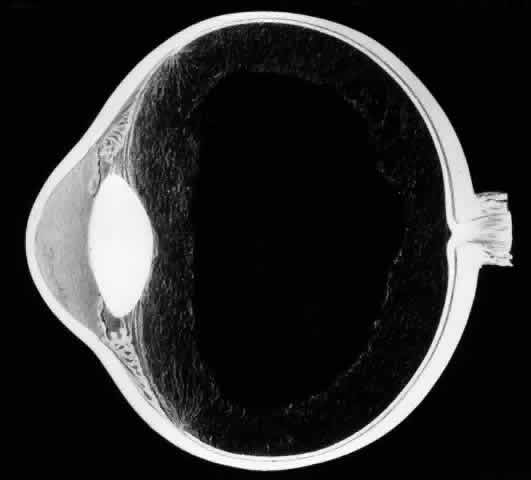

The earliest biomicroscopic changes preceding the development of a giant retinal tear were syneresis and liquefaction of the vitreous gel, converting the posterior and central portions of the vitreous body into a large lacuna (Fig. 14). Later, the anterior gel became condensed, and its posterior aspect formed an equatorially oriented membrane extending across the vitreous cavity (Fig. 15). This membrane did not oscillate with ocular movements, suggesting that it was under tension. Marked contraction of this membrane seems responsible for tearing the retina along the posterior border of the vitreous base (Fig. 16). Liquefied vitreous gel facilitated inversion of the posterior retinal flap (Fig. 17).

Fig. 14. The earliest biomicroscopic change in the vitreous prior to the development of a nontraumatic giant retinal break is liquefaction of the vitreous gel, which converts the central portion of the vitreous gel into a large lacuna.

Fig. 15. In later biomicroscopic changes preceding a nontraumatic giant retinal break, the anterior vitreous gel becomes condensed and a membrane forms its posterior aspect.